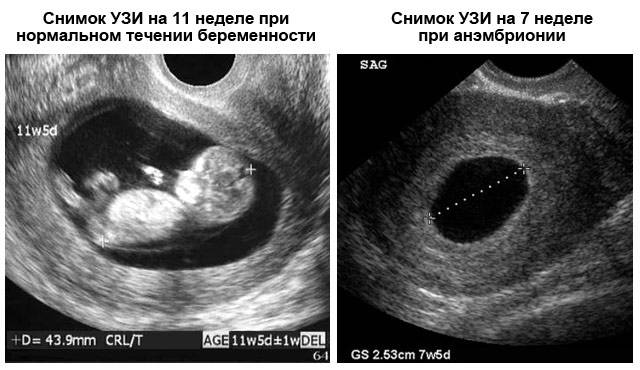

Точный диагноз анэмбрионии

Для точного диагноза анэмбрионии необходимо провести ультразвуковое исследование. Это позволит определить наличие эмбриона и его сердцебиение.

Анэмбриония (отсутствие эмбриона в плодном яйце) может быть диагностирована уже на 5-6 неделе беременности, в случае проведения обследования на высокоразрешающей аппаратуре. Срок беременности рассчитывается с первого дня последних месячных. То есть увидеть эмбрион врач сможет уже на 1-2 неделе задержки.

На вопрос — может ли плодное яйцо расти без эмбриона, можно ответить с уверенностью – да. При анэмбрионии, как правило, эмбрион вырастает до размера всего 1-2 мм, и практически никогда не виден при УЗИ-обследовании. Если плодное яйцо достигло диаметра 16-20 мм и продолжает расти (в этом случае за счет скопления в нем жидкости), а эмбриона не видно – врач констатирует анэмбрионию. Если плодное яйцо имеет меньшие размеры, но деформировано – это не повод ставить угрозу выкидыша или замершей беременности, так как деформировано оно бывает, чаще всего, из-за локального тонуса матки, безобидного состояния, возникающего как реакция на прикосновения УЗИ-датчика.

На экране монитора пустое плодное яйцо визуализируется как черное пятно неправильной формы, как правило меньше по размерам, чем должно быть по сроку беременности. Иногда специалист видит нормальное плодное яйцо округлой формы, но желточный мешок в нем отсутствует. На первых неделях беременности ультразвуковое обследование обладает низкой информативностью, поэтому рекомендуется проходить первое УЗИ на 10–12 неделе – в это время плод уже четко виден.

- анэмбриония – патология, которая характеризуется отсутствием эмбриона в плодном яйце, которое увеличивается в объеме, может наполняться серозной жидкостью, но при этом не содержать внутри эмбриона. Выявить такую патологию можно только с помощью ультразвукового исследования не быстрее чем на седьмой неделе после предполагаемого зачатия.